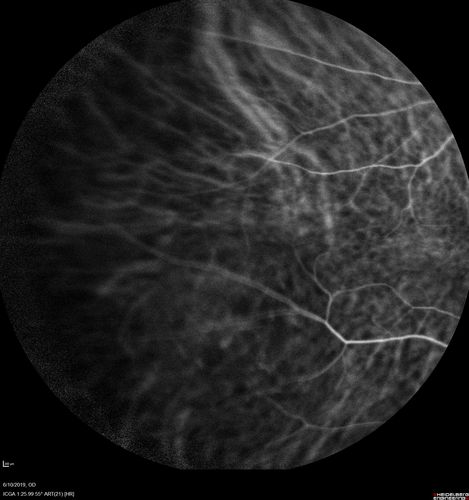

88 year old female with 2.5 mm elevated choroidal melanoma and melanosis oculi.  She also has geographic atrophy from AMD.  The right eye is the better eye with 20/40 vision.  After observation with growth, brachytherapy was done.